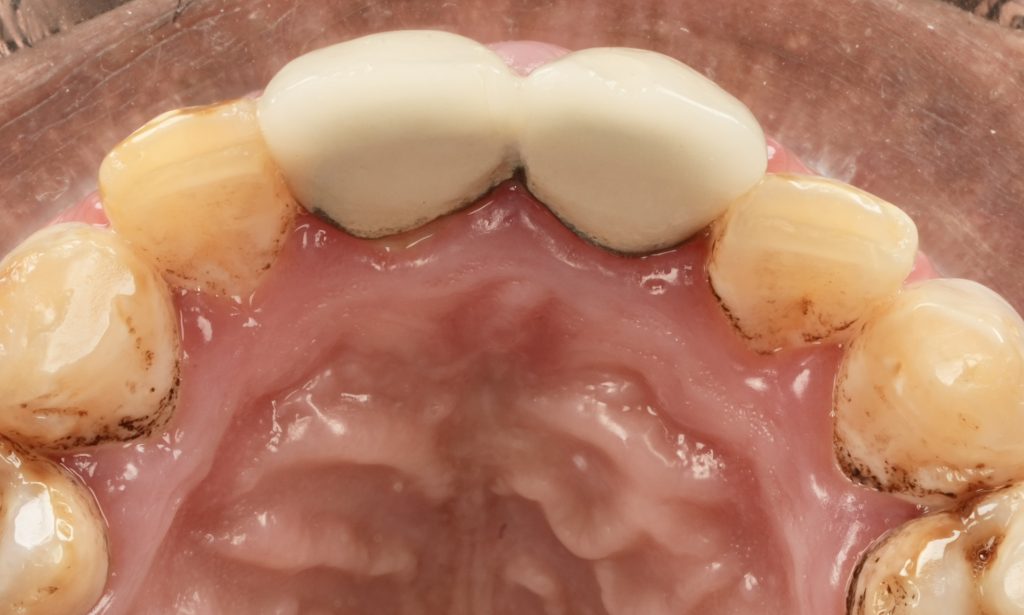

Each veneer was etched with 9 % HF acid for 20 seconds, silanated, and dried. Teeth were treated with 37 % phosphoric acid and universal adhesive (Clearfil Universal Bond Quick). Light-cure resin cement (Variolink Esthetic LC) was applied under full-arch rubber-dam isolation. Excess cement was removed and polymerization performed for 40 s per surface (Fig 4).